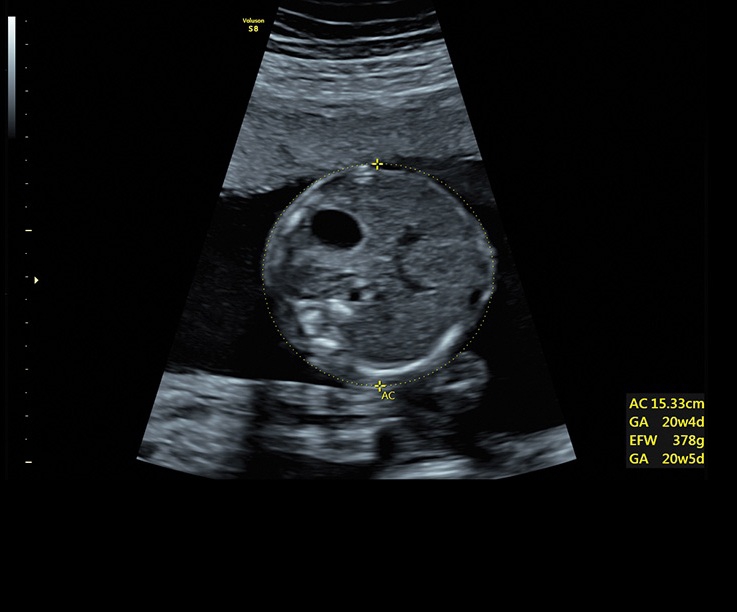

• Технология автоматической фетометрии в 2D режиме (SonoBiometry): Эта технология позволяет автоматически измерять бипариетальный размер, окружность головы, окружность живота, длину бедра и плеча плода, обеспечивая точные и надежные измерения.

• Технология SonoRenderlive: Эта технология облегчает получение 3D/4D изображений путем автоматического изменения положения плоскости визуализации в зависимости от движений плода. Она позволяет получить реалистичные и объемные изображения, что полезно для демонстрации плода будущим родителям и для дополнительного анализа.